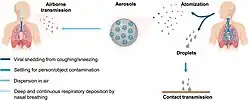

COVID‑19 transmission occurs when infectious particles are breathed in or come into contact with the eyes, nose, or mouth. The risk is highest when people are in close proximity, but small airborne particles containing the virus can remain suspended in the air and travel over longer distances, particularly indoors. Transmission can also occur when people touch their eyes, nose, or mouth after touching surfaces or objects that have been contaminated by the virus. People remain contagious for up to 20 days and can spread the virus even if they do not develop symptoms.[16]

Infected people exhale those particles as they breathe, talk, cough, sneeze, or sing.[86][87][88][89] Transmission is most likely at closer range but, can also occur can occur over longer distances, particularly indoors.[86][90]

The virus spreads through virus-laden fluid particles, or droplets, which are created in the respiratory tract, and they are expelled by the mouth and the nose. There are three types of transmission: "droplet" and "contact", which are associated with large droplets, and "airborne", which is associated with small droplets.[91] If the droplets are above a certain critical size, they settle faster than they evaporate, and therefore they contaminate surfaces surrounding them.[91] Droplets that are below a certain critical size, generally thought to be <100μm diameter, evaporate faster than they settle; due to that fact, they form respiratory aerosol particles that remain airborne for a long period of time over extensive distances.[91][86]

Infectivity can begin four to five days before the onset of symptoms.[92] Infected people can spread the disease even if they are pre-symptomatic or asymptomatic.[93] Most commonly, the peak viral load in upper respiratory tract samples occurs close to the time of symptom onset and declines after the first week after symptoms begin.[93] Current evidence suggests a duration of viral shedding and the period of infectiousness of up to ten days following symptom onset for people with mild to moderate COVID-19, and up to 20 days for persons with severe COVID-19, including immunocompromised people.[94][93]

Infectious particles range in size from aerosols that remain suspended in the air for long periods of time to larger droplets that remain airborne briefly or fall to the ground.[95][96][97][98] Additionally, COVID-19 research has redefined the traditional understanding of how respiratory viruses are transmitted.[98][99] The largest droplets of respiratory fluid do not travel far, but can be inhaled or land on mucous membranes on the eyes, nose, or mouth to infect.[97] Aerosols are highest in concentration when people are in close proximity, which leads to easier viral transmission when people are physically close,[97][98][99] but airborne transmission can occur at longer distances, mainly in locations that are poorly ventilated;[97] in those conditions small particles can remain suspended in the air for minutes to hours.[97][100]Virology